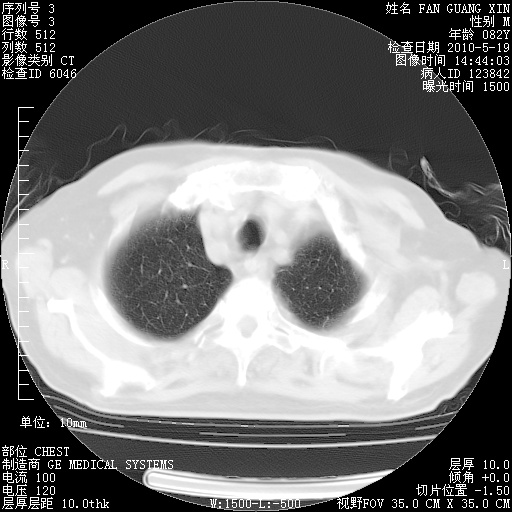

可改为口服强的松40-50mg/d治疗,若病情仍稳定,胸部阴影不再吸收可逐渐减量